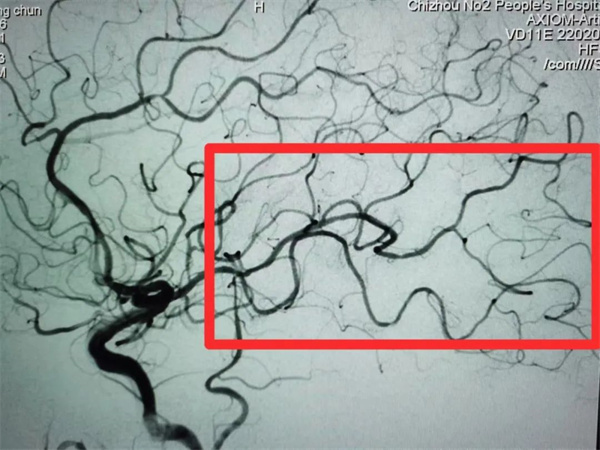

张大爷今年82岁2023年10月13日上午10时30分在劳动中突然出现失语伴右侧上下肢无力,发病2小时即被家人送达我院,医院立即启动“急性脑卒中救治绿色通道”,神经内科方茹主治医师指挥迅速完成头颅MRI、头颈CTA等相关检查诊断为“大面积脑梗死、心房颤动、高血压病、左侧大脑中动脉M1段下干闭塞(图一)”,NIHSS评分10分,因张大爷既往出现过脑出血,有静脉溶栓禁忌,而有机械取栓介入手术指征,方茹主治医师迅速将张大爷病情汇报给动脉盛守权主任医师取栓团队,经评估并与患者家属沟通,同时积极完善术前准备。15:50,手术在全麻下开始,15:56完成股动脉穿刺,16:50抽吸出血栓一枚,闭塞的血管成功再通(图二)。术后给予密切监护、抗血小板治疗后改抗凝治疗、稳定斑块、脑保护、对症等治疗处理10月24日,张大爷出院时可独立行走,遗留轻度失语。